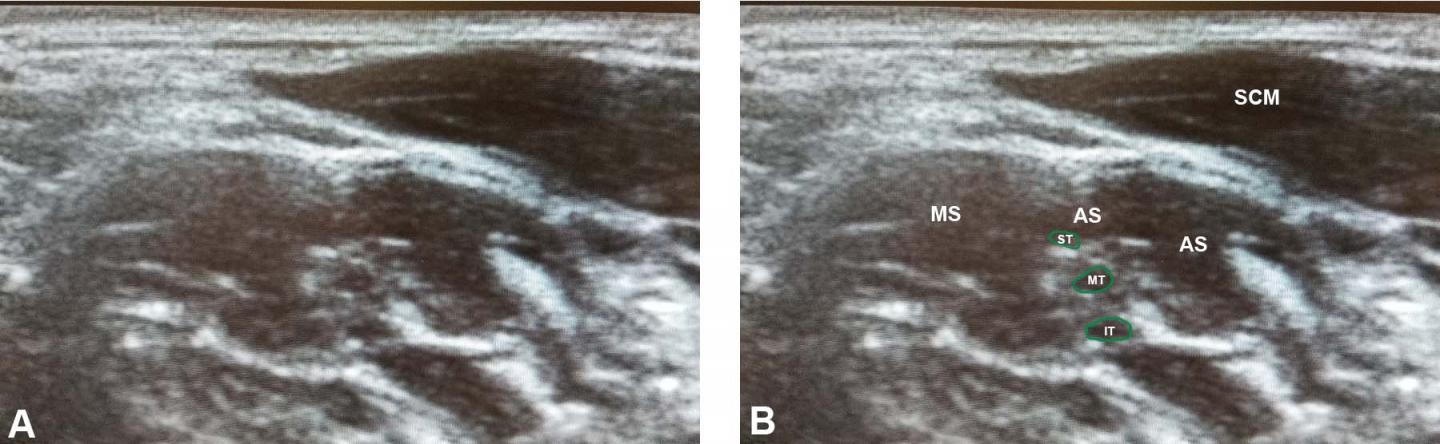

Using a large sample of cadavers, they found that as many as 50% of people may have a clinically relevant variation in the neck, in which some of the brachial plexus pierces the anterior scalene muscle. This surprisingly common pattern has profound clinical implications, because it may result in impingement of the nerves and consequently predispose patients to nTOS. To determine whether these variations were significantly correlated with nTOS symptoms, they recruited a sample of volunteer subjects who filled out a detailed questionnaire describing any neurogenic neck or arm symptoms they had, including those typically found in nTOS, and subjected them to traditional nTOS diagnostic positional testing. The brachial plexus and scalene muscles of each subject were then evaluated using ultrasound. The team found that ultrasound can reliably reveal brachial plexus piercing variations, and that these variations are found at significantly higher rates in subjects with nTOS symptoms. In fact, the ultrasound results were more reliable at diagnosing nTOS than the traditional tests.